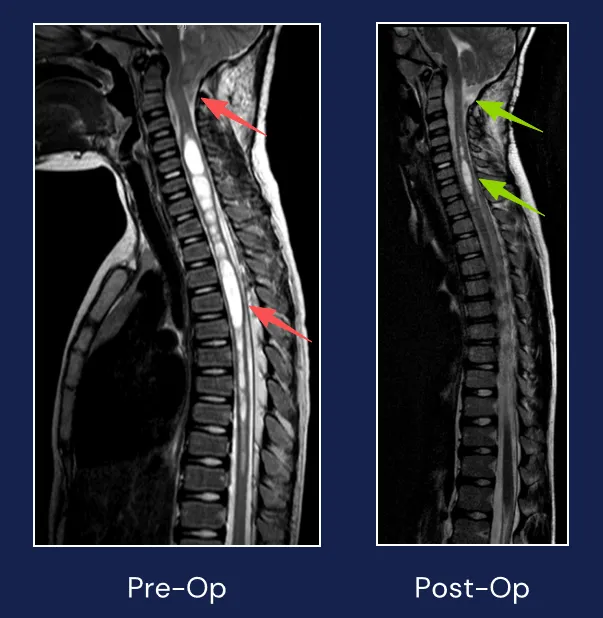

因为发育迟缓,8岁的玮玮在家长的陪同下来到医院。 她走路还总是摔倒,医生,这到底是怎么回事? 面对神情焦急的家长,医生安慰道:孩子有轻度的脊柱侧弯,要是不放心,可以去拍个核磁...